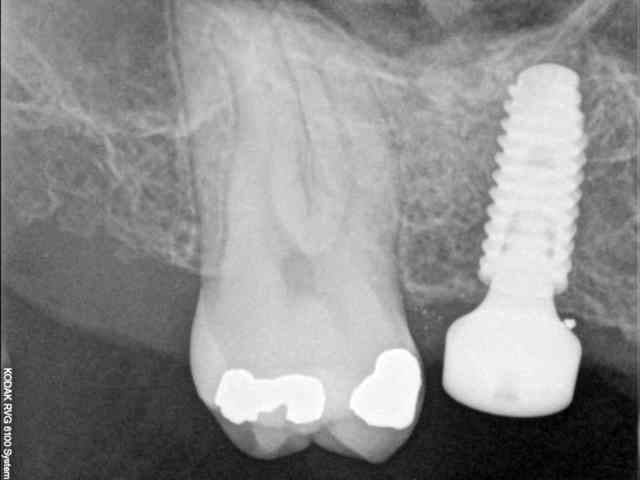

quasiment 6 mois entre les deux interventions (sinus lift et mise à jour)

c'est surtout la qualité des trabéculations osseuses qui m'interpelle.

d'habitude, on voit toujours un peu de particules, ici, c'est vraiment top.

une toute petite remarque, le point blanc sur la radio avec pilier de cicatrisation.

tu as raison, mais on le voit dés les premières radios post extraction.

j'en déduis donc que j'ai bossé comme un cochon pendant cet acte et qu'une inclusion (amalgame ?) est restée dans la gencive.

je crois que c'est la première fois que je vois une cliché radio à quelques mois post-op avec ce matériau et le résultat semble excellent.